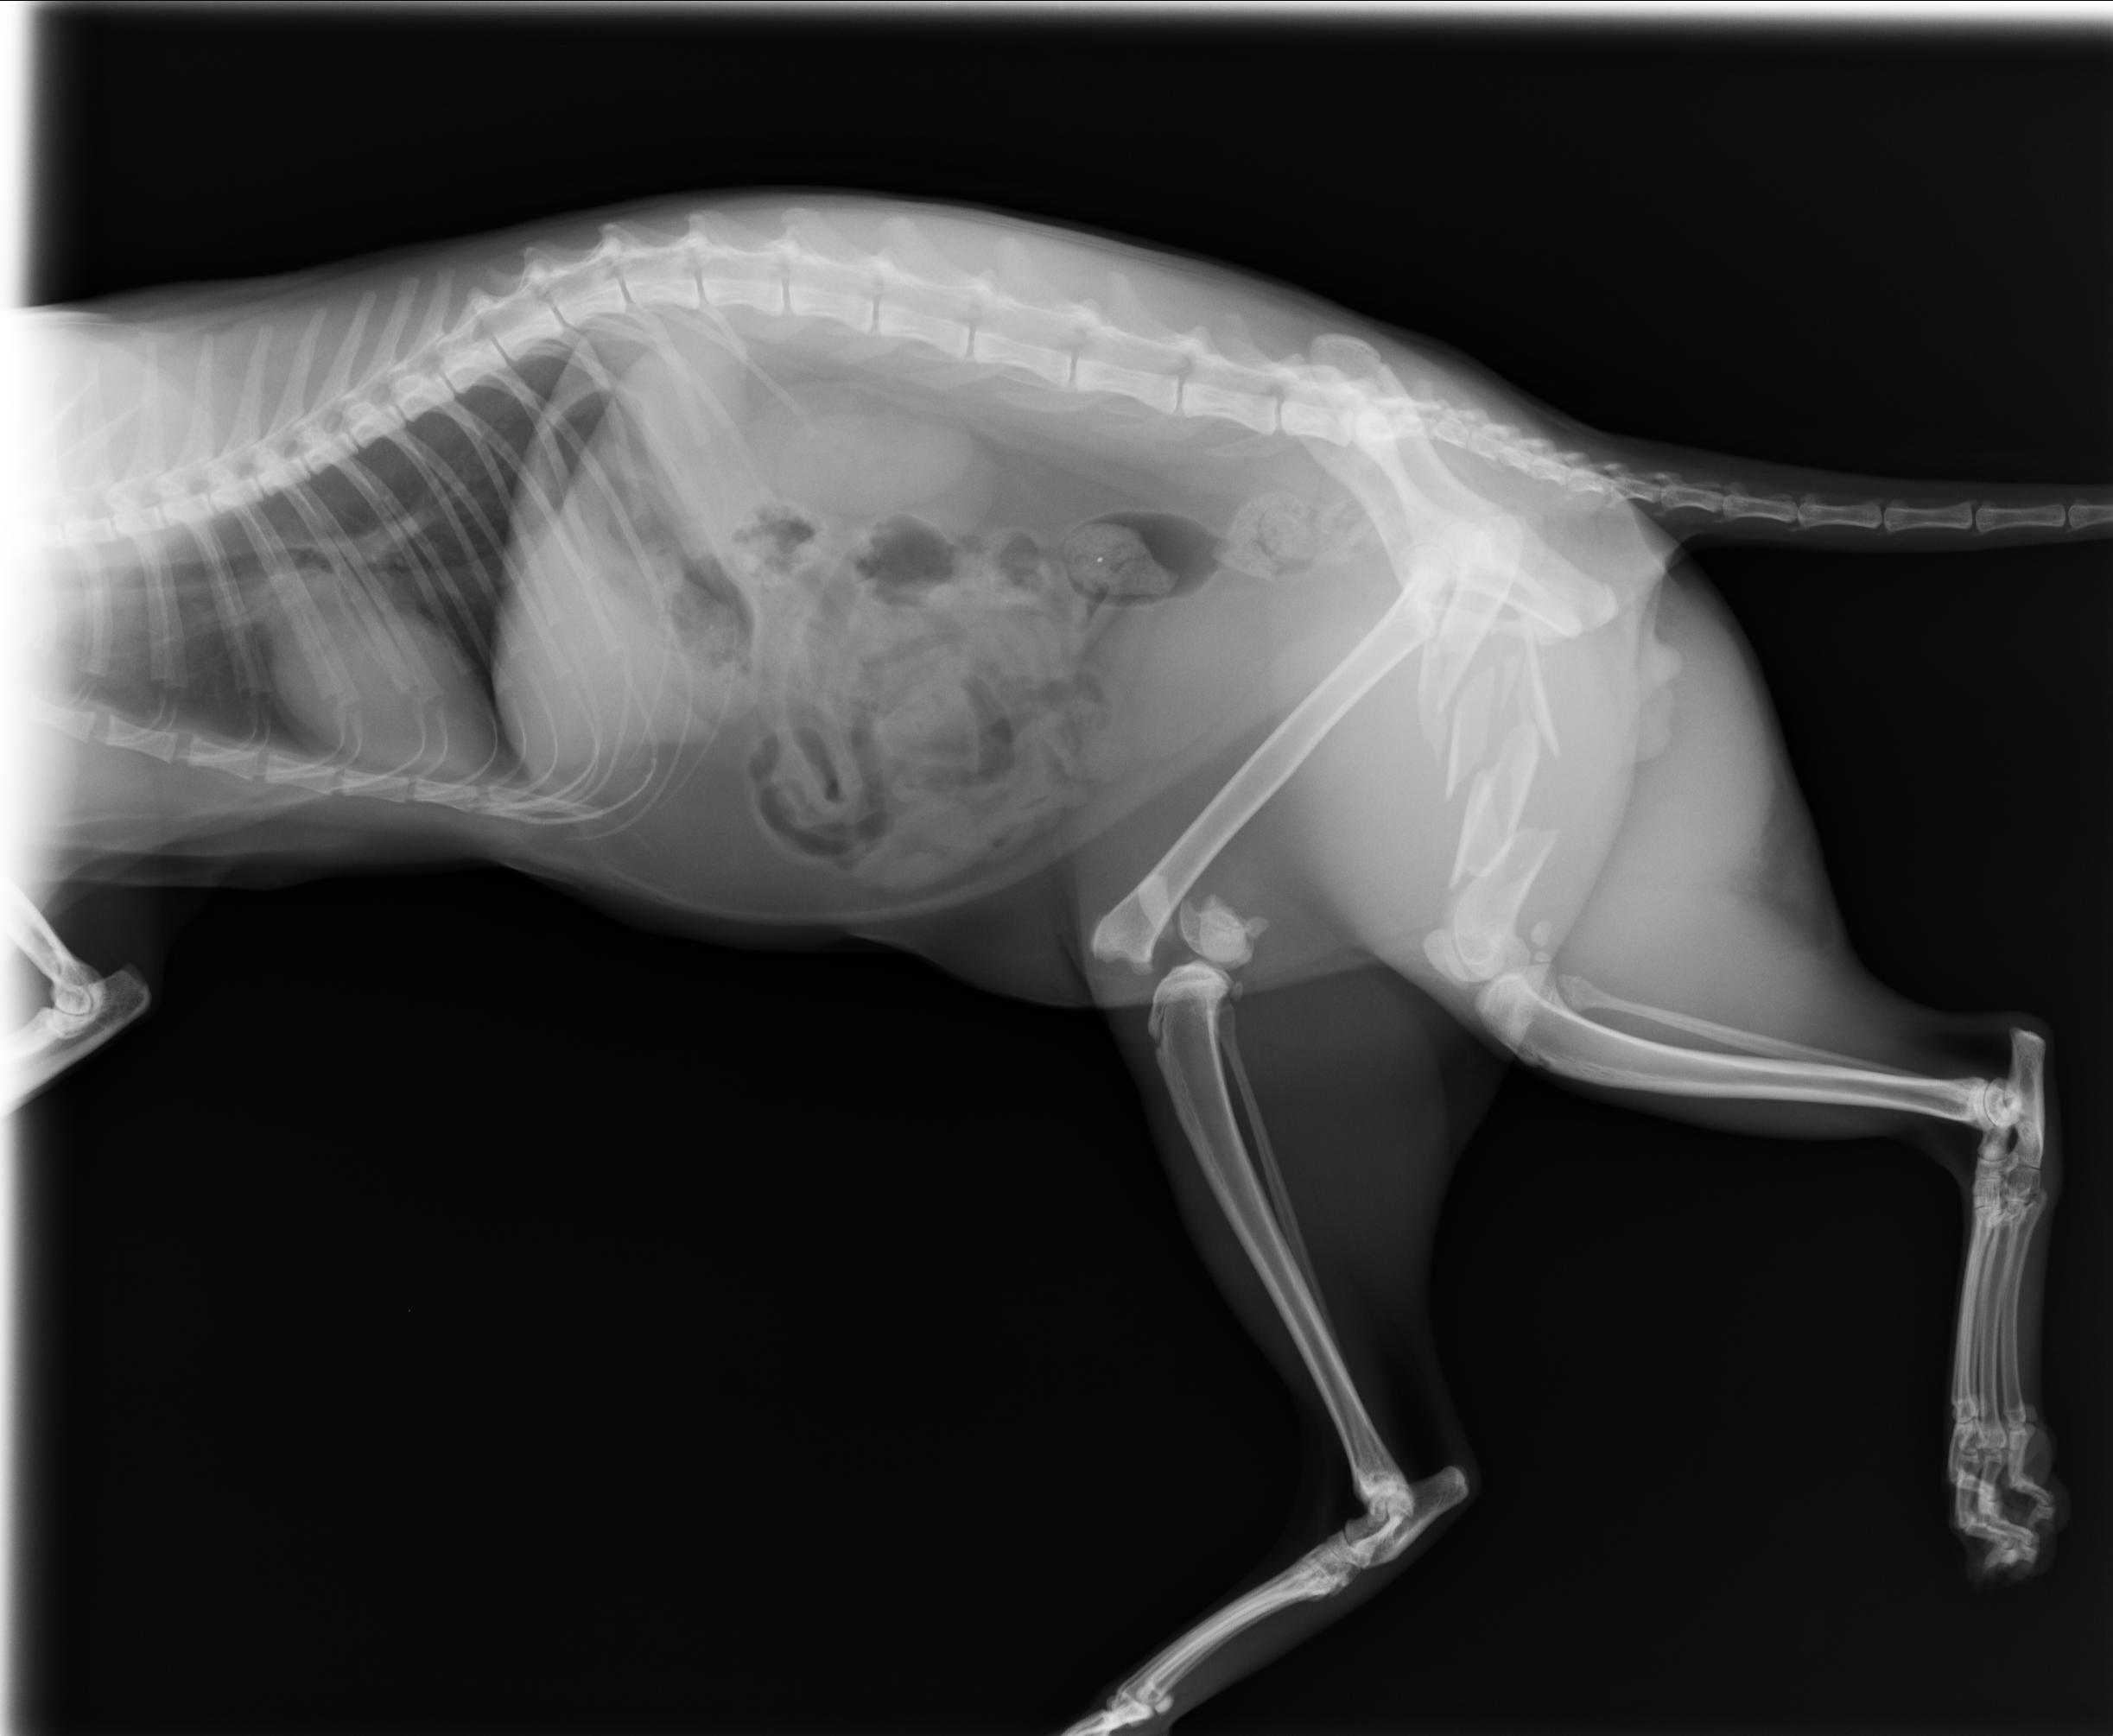

已完成醫助款案例 |